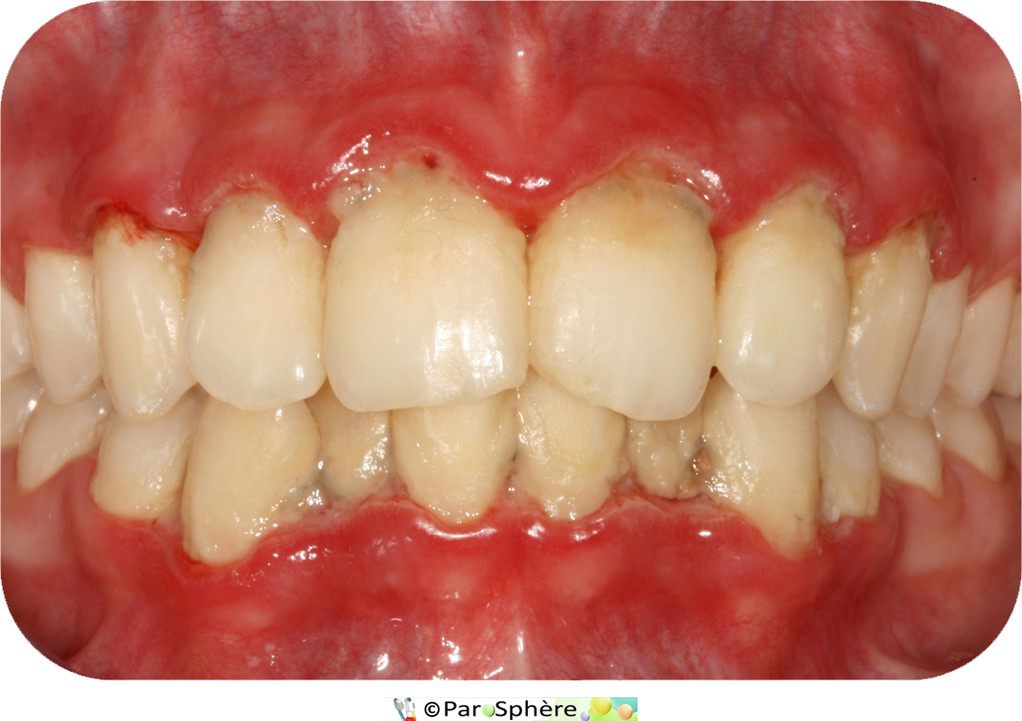

Cette jeune patiente, âgée de seulement 17 ans présente une parodontite ulcéro-nécrotique caractérisée par une importante inflammation gingivale, des saignements spontanés (en haut à sa droite), des douleurs vives l'empêchant de brosser et une desquamation de la gencive entre les dents.

La deuxième montre l'aspect clinique  2 semaines après traitement parodontal.

Le traitement s'est étalé sur 2 semaines et a consisté en :

• une prescription d'antibiotiques,

• l'apprentissage d'une méthode de brossage efficace (brosse à dents très souple, puis souple),

• deux séances de détartrage, surfaçage radiculaire et polissage.

Un suivi régulier est alors nécessaire pour éviter toute récidive.